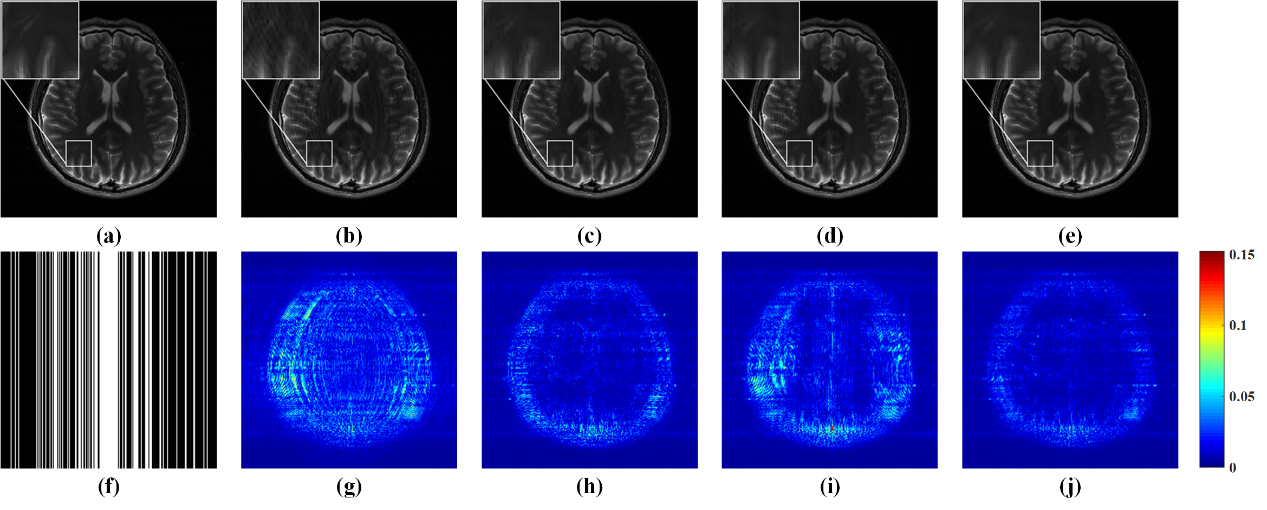

图 2. 3倍加速下的4通道人脑数据重建结果及误差。(a)全采样数据参考图像;(b-e) GRAPPA、-SPIRiT、ALOHA和所提方法的重建图像;(f)3倍加速的采样模板;(g-j)相应的重建误差分布图。(b-e)图的相对二范数误差RLNE分别为:0.1335,0.0866,0.1117,0.0735。

与前沿的并行成像磁共振图像重建方法相比,所提方法的重建图像误差最低,能在抑制采样伪影的同时,很好地保留图像的细节。这意味着,在保证图像同等质量的情况下,所提方法可以进一步降低采样数据量,从而进一步加速扫描过程。此外,所提方法对于并行成像中的校准数据量鲁棒。在扫描过程因实验条件限制无法采集足量校准信号情况下,所提方法仍能可靠重建图像。这给图像扫描选择不同的采样模板提供了很大的灵活性,可以适用于更多的成像场景中。